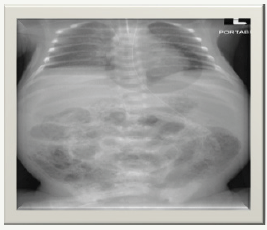

k) On day 7 of life, he was noted to have abdominal distension that was rapidly progressive to a shiny red abdomen with increased gastric aspirates (Figure 2 & 3).

Figure 2:

Figure 3: